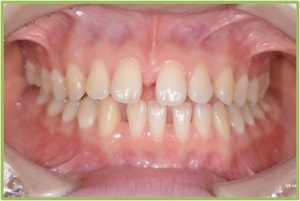

正中離開🔸前歯の1番目の歯が左右に離れる(離開する)

の原因となる事があります🦷